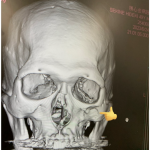

眼底骨折、左頬骨陥没骨折、鼻骨骨折と大怪我だ@shrekbonsai